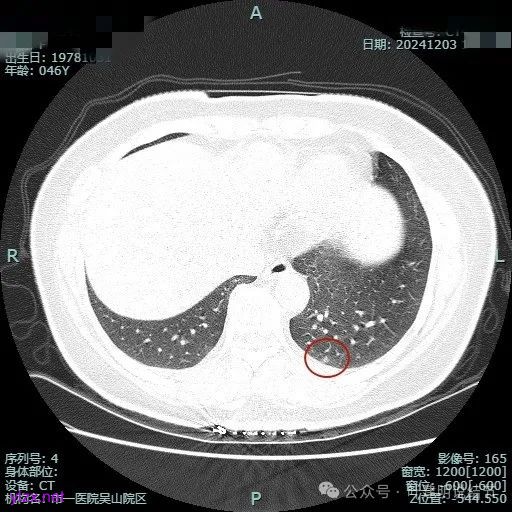

病灶2:

右中叶内侧段可见混合密度结节,大部分实性,形态与下叶背段的类似。

病灶3:

左下叶基底段微小结节,也是混合密度偏实性,瘤肺边界稍不清,与右侧的是类似形态的。